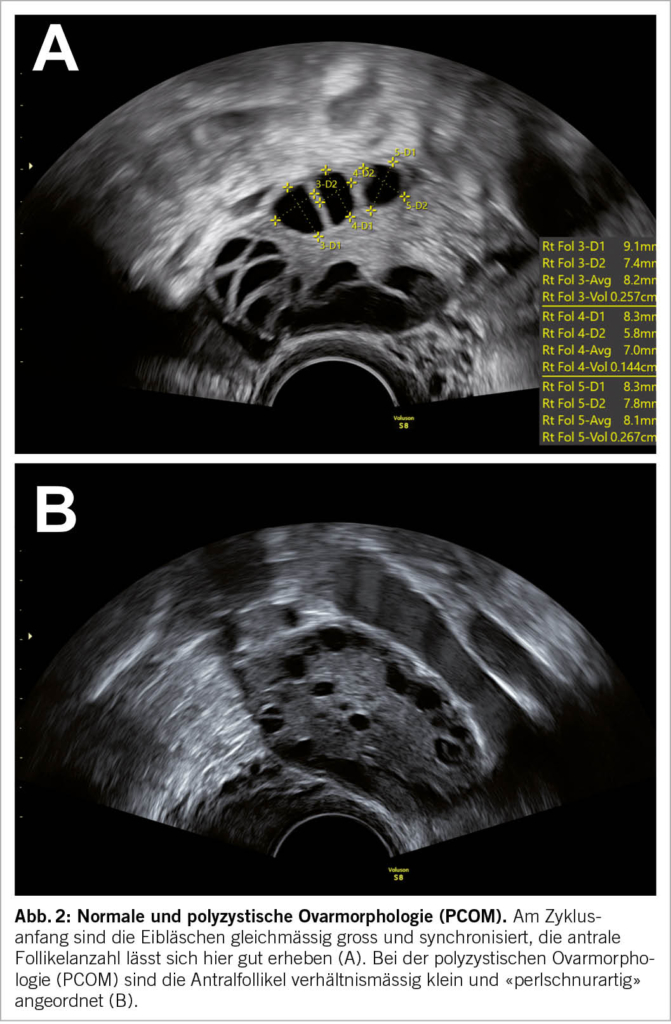

Zusätzlich zum Zyklusmonitoring lassen sich weitere sonographische Untersuchungen durchführen, um die individuelle Fertilität einschätzen zu können: Bei der «Hydrosonographie» (Abb. 4A) wird simultan zur Ultraschalluntersuchung sterile Kochsalzlösung über einen in den Zervikalkanal eingebrachten Katheter in die Gebärmutterhöhle gespült. Das Cavum uteri dehnt sich hierdurch echoleer auf, wodurch bestimmte schleimhautverändernde Pathologien besser zu erkennen sind (z.B. kleinste Polypen, Synechien, submuköse Myome). Bei der «Hystero-Foam-Salpingography (HyFoSy)» (Abb. 4B) wird ebenfalls ein Katheter in die Zervix eingebracht. Über diesen wird während der Ultraschalluntersuchung eine schaumartige, kolloidhaltige Lösung in Gebärmutterhöhle und konsekutiv Eileiter eingespritzt. Der Fluss dieser sonographisch echoreichen Lösung kann dynamisch nachverfolgt werden, um eine Eileiterdurchgängigkeitsdiagnostik zu ermöglichen. Die Hydrosonographie und die HyFoSy sollten präovulatorisch durchgeführt werden. Vor Durchführung sollten mikrobiologische und zytologische Abklärungen bei der Patientin erfolgt sein, um ein mögliches Verschleppen von Keimen und dysplastischen Zellen zu vermeiden. Bei Bedarf ist eine Kombination der beiden Untersuchungen möglich.